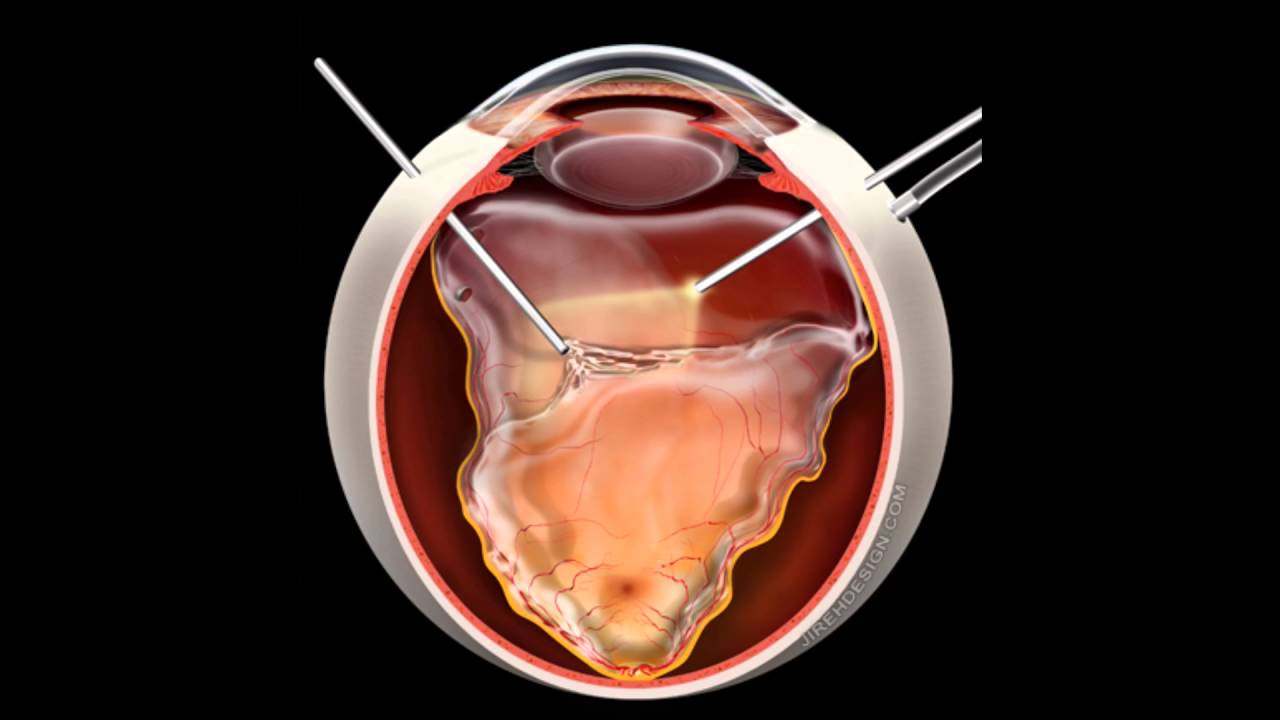

انفصال الشبكية يعتبر حالة طارئة يجب علاجها بأقصى سرعة ممكنة، ويعود هذا إلى حدوث قطع في الشبكية، مما يسبب تسرب سوائل خلفها، حيث ينتج عن هذه الحالة انفصال الشبكية، ومع حدوث ذلك تنقطع الإمدادات الدموية المحملة بالعناصر الغذائية والأكسجين عن الشبكية، وبالتالي تضعف الرؤية.

عملية جراحة انفصال الشبكية من أهم طرق العلاج، فإن نسبة نجاح عملية انفصال الشبكية هي أكثر ما يهم المرضى، توجد نسبة 90% لإعادة ربط شبكية العين المنفصلة خلال عملية جراحية واحدة، ولكن الهدف الأساسي هو تحسين النظر في عينك، أي حتى لو كانت عملية انفصال الشبكية ناجحة، لا تكون الرؤية بنفس مستواها كما كانت قبل أن تنفصل الشبكية، ولكن من المفترض أن تكون جيدة، والسبب الرئيسي لعدم نجاح عملية انفصال الشبكية هو تشكيل أنسجة ندبة تعيد انفصال الشكية بعد فترة ونسبة إعادة إجراء عملية انفصال الشبكية مرة أخرى قليلة، فالخطر الأكبر لعدم النجاح يكون خلال الأشهر الثلاثة الأولى بعد الجراحة، ويتم مراقبة ذلك جيداً من قبل الطبيب بعد إجراء العملية.